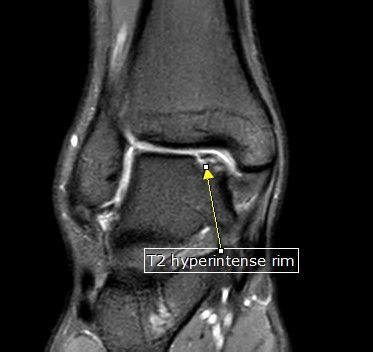

Alright, let’s kick things off by really understanding what an osteochondral injury is at its core. Picture your joint – whether it’s your knee, ankle, elbow, or even your shoulder – it’s covered in a smooth, slippery tissue called articular cartilage . This cartilage, guys, is absolutely vital; it acts like a natural cushion and lubricant, allowing your bones to glide over each other without friction, absorbing shock from daily activities and keeping everything moving smoothly. Right underneath that cartilage is a layer of bone, known as the subchondral bone . Together, this dynamic duo – the cartilage and the subchondral bone – form what we call the osteochondral unit . Now, an osteochondral injury occurs when there’s damage to both this articular cartilage and the underlying subchondral bone. It’s not just a tear in the cartilage or a bone bruise; it’s a combined injury that can range from a tiny crack or a small divot to a full-blown chunk of cartilage and bone breaking loose. This can create a defect or a lesion on the joint surface, disrupting that smooth, pain-free movement you’re used to. Think of it like a pothole forming on a perfectly smooth road – suddenly, the ride gets bumpy, and the integrity of the surface is compromised. These injuries can vary significantly in their severity, from superficial scrapes to deep, full-thickness defects that expose the underlying bone, making them quite complex to manage. The challenge with cartilage is that, unlike bone, it has a very limited blood supply, which means it doesn’t heal easily on its own. This makes osteochondral injuries particularly problematic and often requires more significant intervention than other types of musculoskeletal damage. The prevalence of these injuries is quite high, especially in active individuals and athletes, given the high impact and rotational forces joints are often subjected to. Understanding this fundamental concept is the first crucial step in grasping why proper diagnosis and treatment are so critical for long-term joint health and function. It’s about protecting those precious joint surfaces so you can keep moving freely and without pain, living your best life every single day. We’ll dive into the specifics of how these injuries happen next, so you can better identify potential risks and take preventive measures.